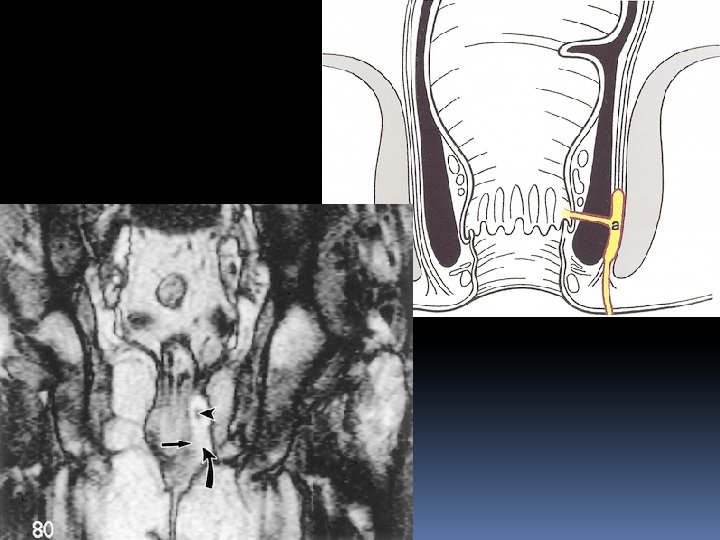

Grade 1 : simple linear intersphincteric fistula

Intersphincteric fistula Axial T 2 W with and without fat saturation The intersphincteric fistula located at 6 o’clock

Intersphincteric fistula